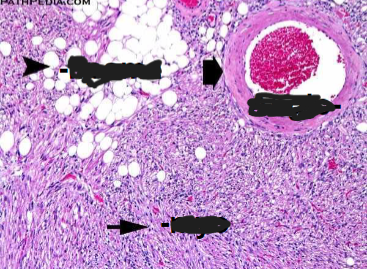

Angiomyolipoma

Benign, but if large may fatally hemorrhage

Neoplasm composed of: Vessels + Smooth muscle + Fat